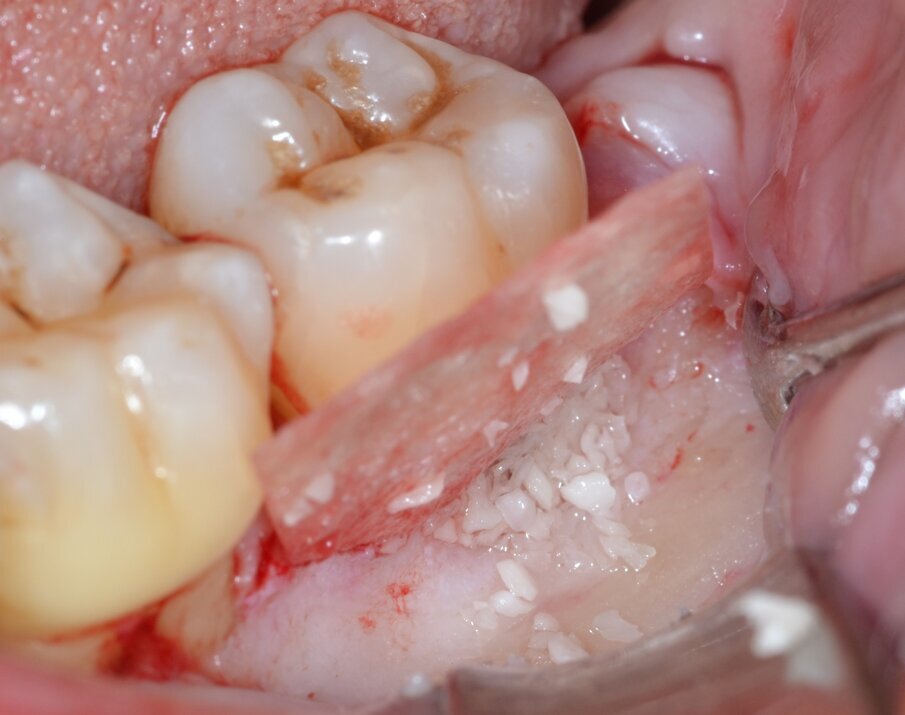

Dopo analgesia locale ottenuta per infiltrazione di Articaina cloridrato 40 mg con epinefrina 1:100.000 viene effettuata l’incisione di accesso secondo la tecnica denominata “Crestal Incision”4 per elevare un lembo a spessore totale che espone l’area interessata dal difetto (Fig. 5). Il debridement e la decontaminazione della superficie radicolare vengono effettuati per mezzo di inserti ultrasonici dedicati (Figg. 6, 7); al completamento di questo tempo chirurgico il difetto è innestato con biomateriale eterologo protetto da una membrana di tipo riassorbibile in pericardio di origine animale che viene fissata sulla cresta ossea mediante pins in titanio allo scopo di stabilizzare il coagulo e guidare la rigenerazione tissutale all’ interno del difetto. La ferita chirurgica è suturata con un filo riassorbibile 6/0 in PGA (Figg. 8-12).

Fig. 10 - Innesto di biomateriale eterologo.

Fig. 11 - Stabilizzazione della membrana barriera mediante pins in titanio.